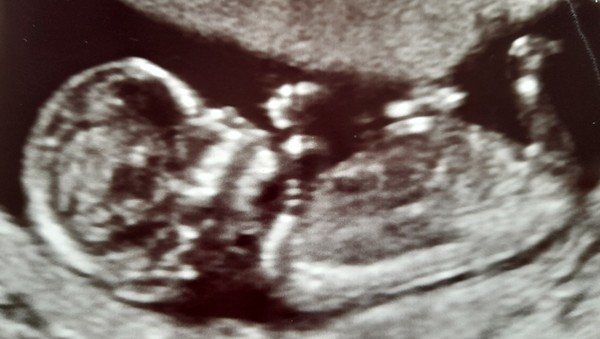

Praying for this sweet child of mine, my 12 week scan pic. 🥰 Will update with results next week. xx

This is beautiful 🤩 Really hope you’re ok. It is so hard to focus on anything else during a time like this. I’m praying all goes well with your results. Being in limbo can be horrible. I think I took for granted during my first pregnancy that I was low risk for everything and all the tests were fine looking back xx

That is a beautiful scan picture @MumOfMiracles. I hope everything goes well for you. x